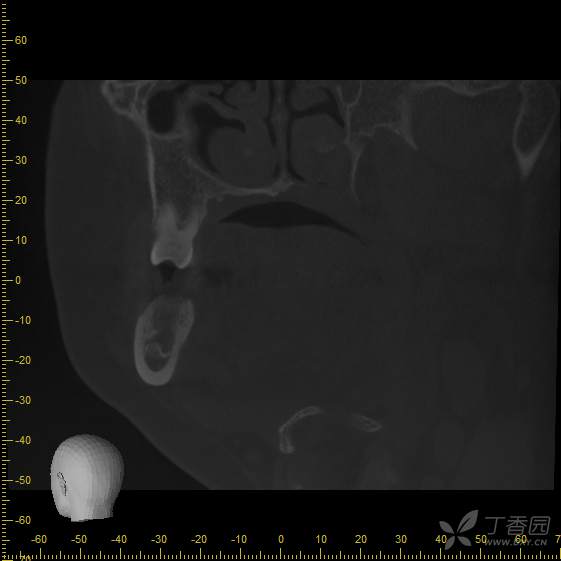

术前cbct,可见36拔牙窝低密度影,牙槽嵴顶骨白线不可见,推理低密度影可能为炎性肉芽组织,矢状位截图,可见牙槽分隔